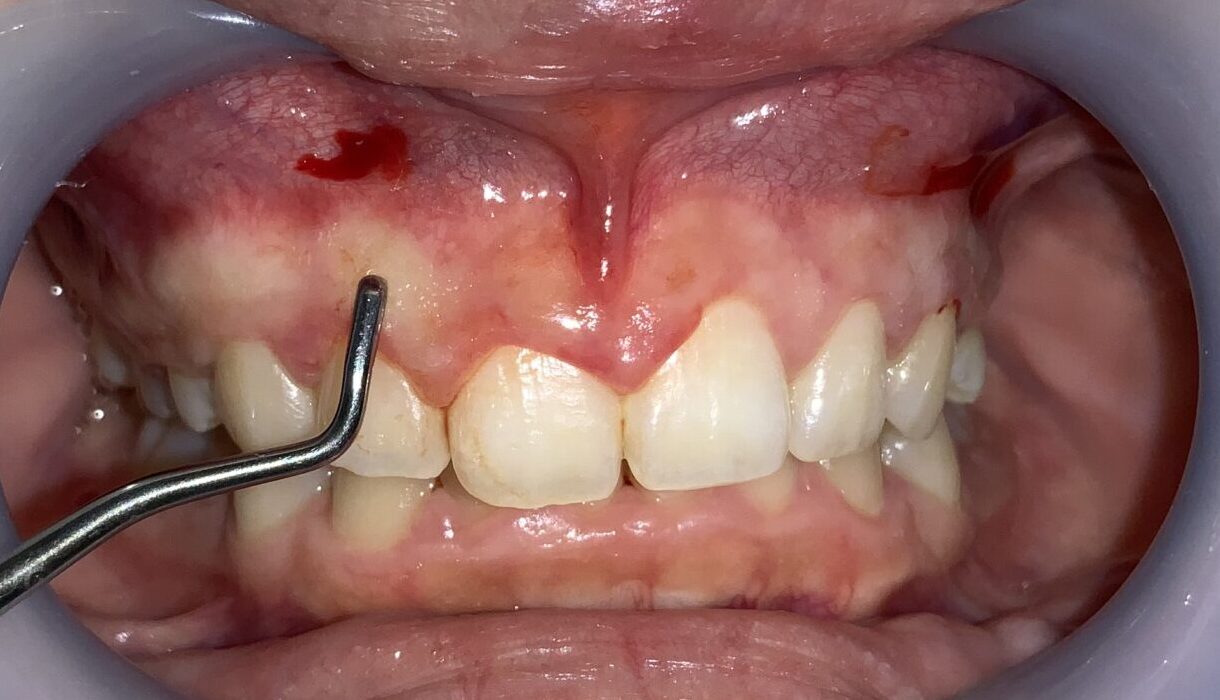

手術前の状態から見て参ります。

歯ぐきが被っており、歯が小さく、左右差があります。歯ぐきが被っている影響で歯ブラシの清掃が届かないので、プラークの堆積や歯ぐきの発赤も認められます。

前歯から順番に検査をして参ります。

歯ぐきの被っている量は相当あります。また、歯ぐきが分厚くて、繊維状に変性をしているようです。しっかり整えましょう。